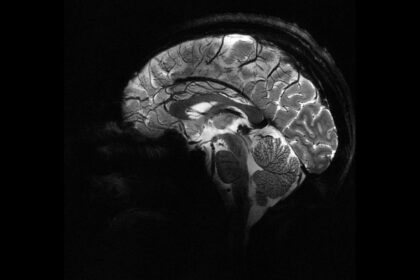

Epilepsiye farklı nedenler yol açsa da, vakaların yaklaşık yüzde 30’u beyindeki yapısal anormalliklerden kaynaklanıyor. Ancak bu lezyonlar, özellikle de beynin kıvrımlarının derinliklerinde saklı olan...